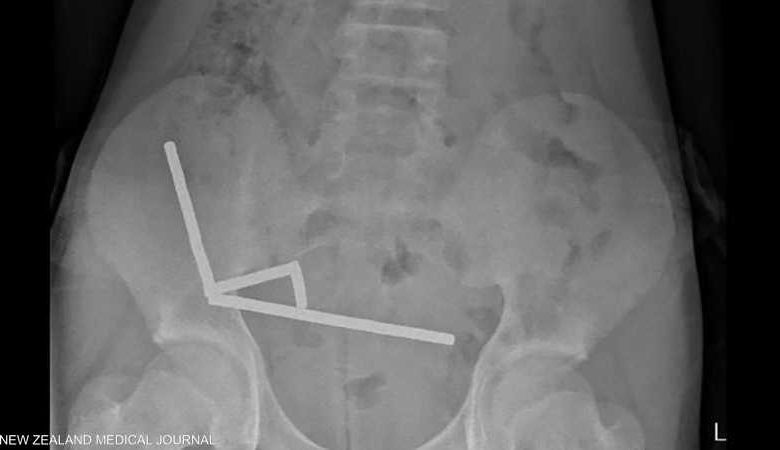

تعرض صبي نيوزيلندي يبلغ من العمر 13 عاماً لخطر الموت بعد أن ابتلع ما يقرب من 100 مغناطيس اشتراها عبر منصة “تيمو” للتسوق الإلكتروني، مما استدعى تدخلاً جراحياً عاجلاً لإنقاذ حياته.

بعد معاناة من آلام بطنية استمرت 4 أيام، نُقل المراهق إلى مستشفى تاورانغا حيث كشفت الفحوصات: · وجود 80 إلى 100 مغناطيس متكتلة في أمعائه · ترتيب المغناطيسات في 4 خطوط مستقيمة · التصاق أجزاء الأمعاء ببعضها بسبب القوى المغناطيسية · موت أنسجة في الأمعاء الدقيقة والغليظة due to الضغط